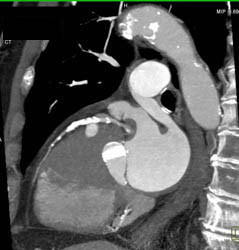

Diagnosis

Diseased LAD